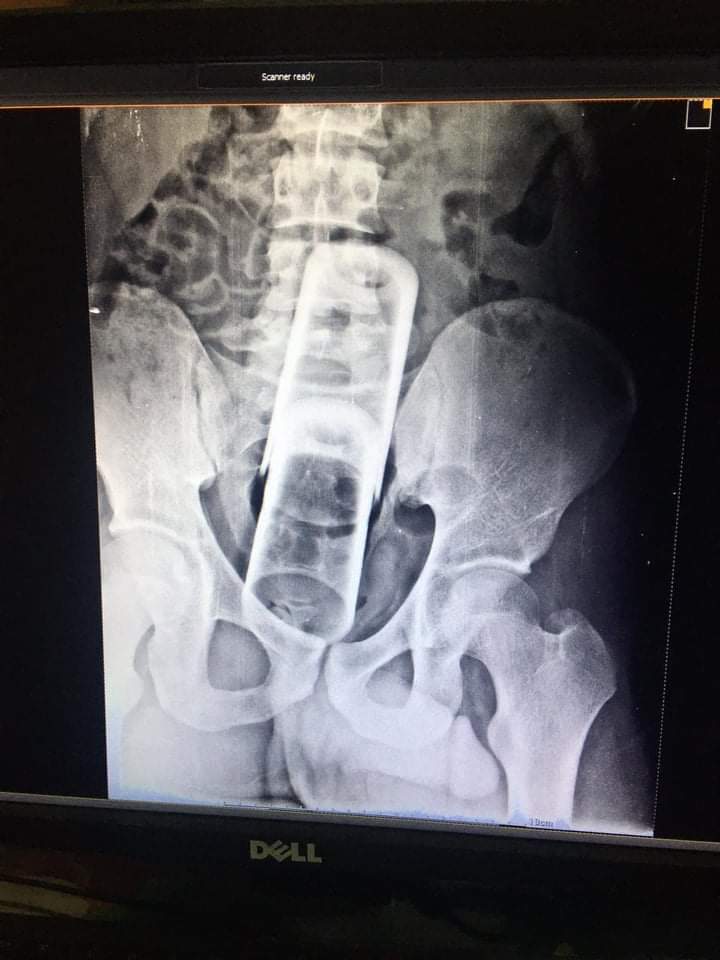

تمكن فريق طبي بمستشفي المنصوة التخصصي فى محافظة الدقهلية من استخراج 2 كوب زجاجي داخل قولون شاب عشريني .

حيث استقبلت مستشفى المنصورة التخصصى شاب عشرينى ادعى سقوطة علي جسم غريب صلب و بفحص المريض تبين وجود 2 كوب زجاجي بالقولون.

وأكد الفريق الطبى أن عملية استخراج الجسم الغريب بعد دخوله للقولون عن طريق المستقيم وصعوبة اخراجة من أسفل أدى إلي عمل فتح جراحى للقولون واستخراج الجسم الغريب وعمل فتحة مؤقته للاخراج وسيتم قفلها وعودة المسار الطبيعى للاخراج بعد عدة اشهر قليلة .